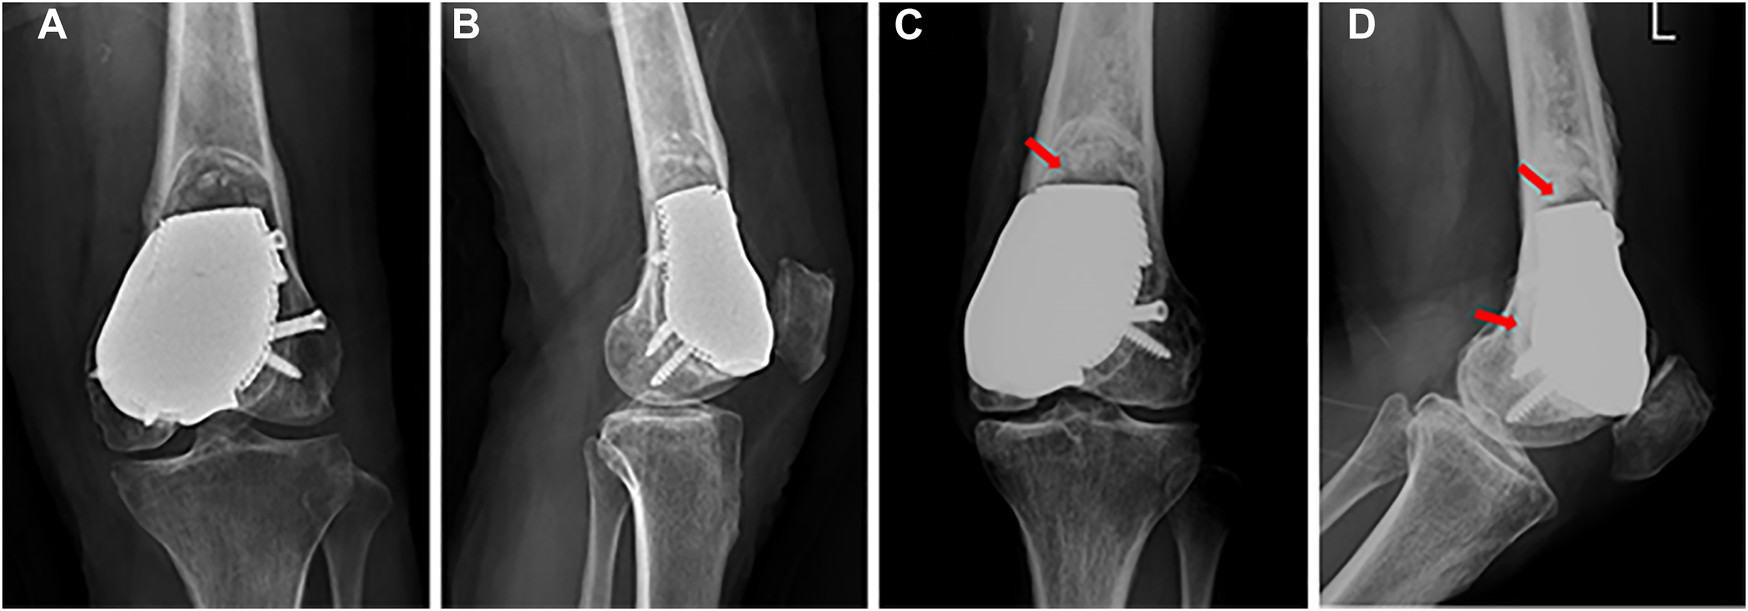

At the last follow-up visit 27 months after surgery, the patient was pain free with full weight-bearing (Video 1). The MSTS score was 29/30, and the VAS score was 0. Knee flexion was 130°, which was better than the initial 88° after surgery for 2 months (Figure 5), and knee extension was normal after surgery. There was no local rejection, indicating good biocompatibility and security of the prosthesis. The X-ray images showed that the prosthesis and screws were stable, and no recurrence was observed in the affected knee 22 months after surgery (Figure 6).

FIGURE 6

(A) Anterior–posterior and (B) lateral X-ray images after surgery. (C) Anterior–posterior and (D) lateral X-ray images 22 months after surgery: the prosthesis and screws are stable, and callus formation is found at the prosthesis-bone interface (red arrow).

Intralesional curettage combining bone graft with internal fixation with or without local adjuvants is the most accepted surgical treatment for grade II GCT around the knee (Kamal et al., 2016), as encountered in our first surgery. Local recurrence, infection, and internal fixation failure are serious events that must be considered (Yu et al., 2010; Xu et al., 2013). Unfortunately, the patient experienced a deep infection after intralesional curettage. Although the deep infection was controlled, the patient suffered severe pain (VAS score of 7) and limited knee function (knee flexion was 50°) due to patello-femoral large cartilage defects. Fortunately, she eventually achieved a satisfactory outcome with a 3D-printed prosthesis, a novel reconstruction method for patello-femoral large osteochondral defects. At the last follow-up, she was pain free with full weight-bearing, the MSTS score improved from 15/30 to 29/30, the VAS decreased from 7 to 0, and knee flexion recovered from 50° to 130°. These values were above the overall MSTS score and ROM after intralesional curettage and wide resection reported in the literature (Ayerza et al., 2009; Kundu et al., 2015), indicating that the 3D-printed prosthesis we used may be useful for patello-femoral osteochondral reconstruction.

Patello-femoral arthroplasty is commonly used for symptomatic patello-femoral osteoarthritis or isolated osteochondral lesions without ligament instability (Cotic et al., 2017; Jeong et al., 2020; Rezzadeh et al., 2020). The patient suffered from patello-femoral large osteochondral defects in our case, but patello-femoral arthroplasty could not achieve mechanical stability because of mass bone defects. Although the cement packing had adequate strength for the bone defects, we failed to reconstruct the patello-femoral cartilage, which led to knee pain; and the bone-cement interface is a non-biological integration, which can lead to secondary degenerative changes and fractures (Kundu et al., 2015; Teng et al., 2019). Consequently, a sclerotic rim was found around the bone-cement interface after 11 months of cement packing. Considering this, a porous endoprosthesis produced by a 3D technique that enables bone ingrowth may solve this problem. Lu et al. (2019) reported a patient treated with a 3D-printed porous implant combined with bone grafting for subchondral GCT of the proximal tibia and found excellent osseointegration between the graft and retained subchondral bone during a follow-up period of 29 months. In our case, we found that the prosthesis was fixed firmly, and that there was callus formation at the prosthesis-bone interface after surgery for 22 months, indicating the feasibility of a 3D-printed porous prosthesis to achieve osseointegration.